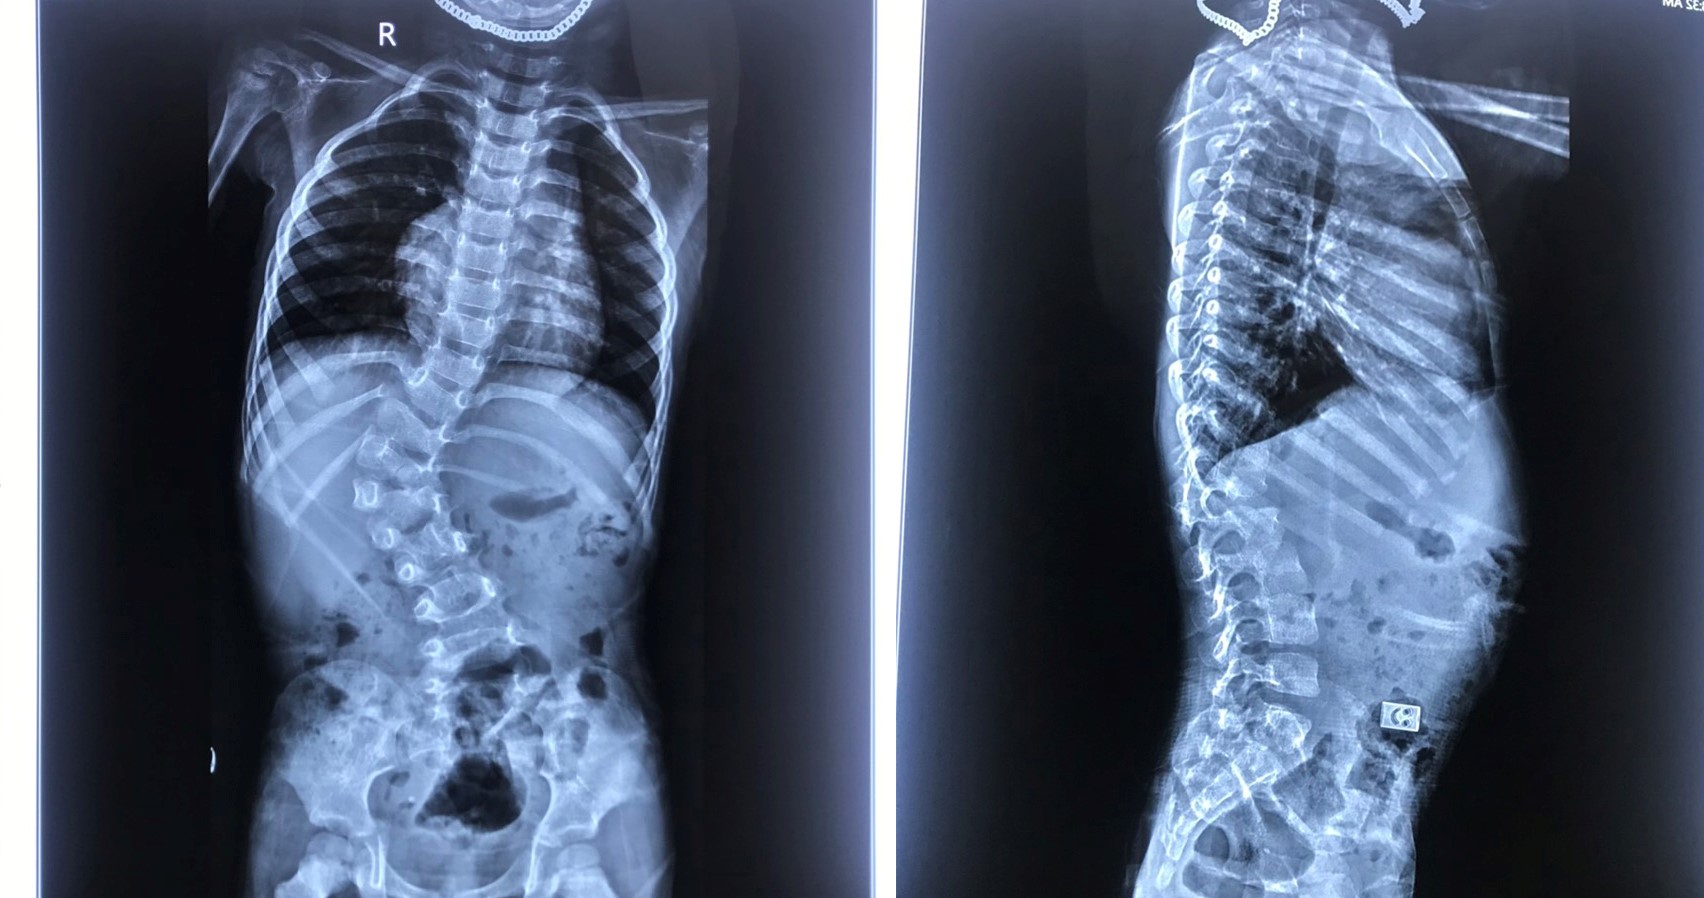

Một cột sống khỏe mạnh giúp cơ thể phát triển cân đối, đồng thời hỗ trợ quá trình tăng trưởng chiều cao diễn ra thuận lợi. Ngược lại, khi cột sống bị ảnh hưởng bởi sai tư thế, thiếu vận động hoặc chế độ dinh dưỡng không hợp lý, trẻ dễ gặp tình trạng cong vẹo, đau lưng sớm và hạn chế phát triển chiều cao tối đa.

Trẻ em thường ngồi cong lưng hoặc cúi đầu quá nhiều khi học bài, đây là nguyên nhân phổ biến dẫn đến gù lưng và vẹo cột sống. Việc sử dụng bàn ghế không phù hợp với chiều cao của trẻ càng làm tình trạng trở nên nghiêm trọng.